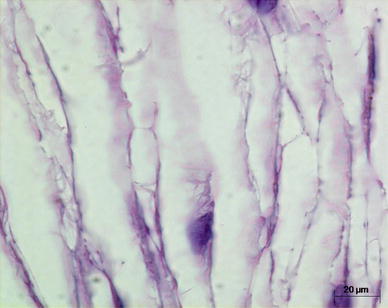

Fig. 2.

A saline-injected tissue section viewed at 100× at the 6-h time point post-challenge, showing no cellular infiltration